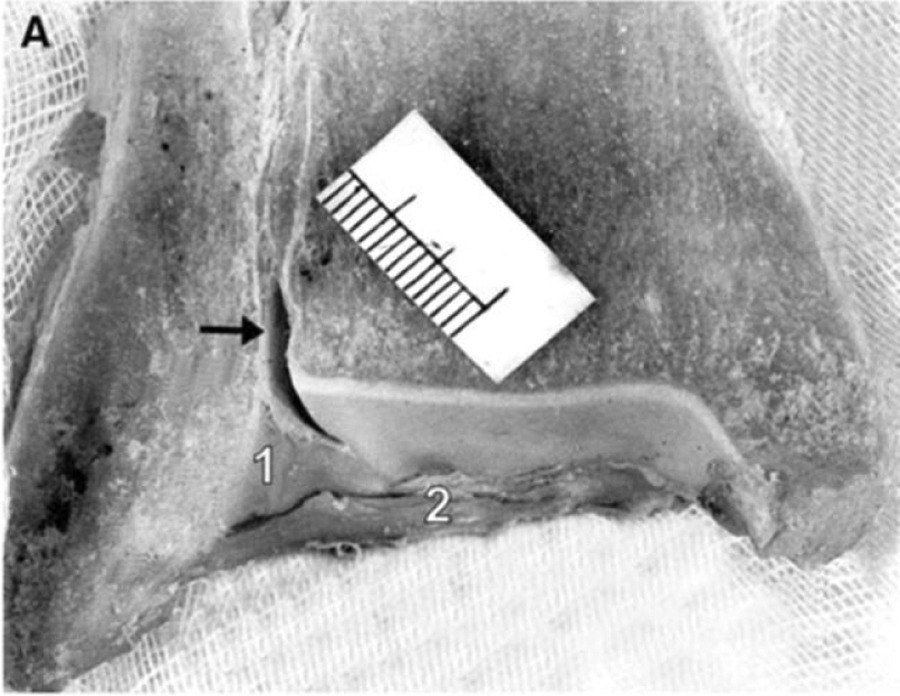

Рис. 8. задняя нижняя большеберцово-малоберцовая связка (ЗНБМС/PITFL), вид сзади. 3D-модель и кадаверные препараты. Два пучка: поверхностный и глубокий (нижняя поперечная связка). Трапециевидная форма, толщина 6 мм, длина 20 мм. Площадка прикрепления на малоберцовой кости — 26,3 мм от верхушки, на большеберцовой — 9 мм.